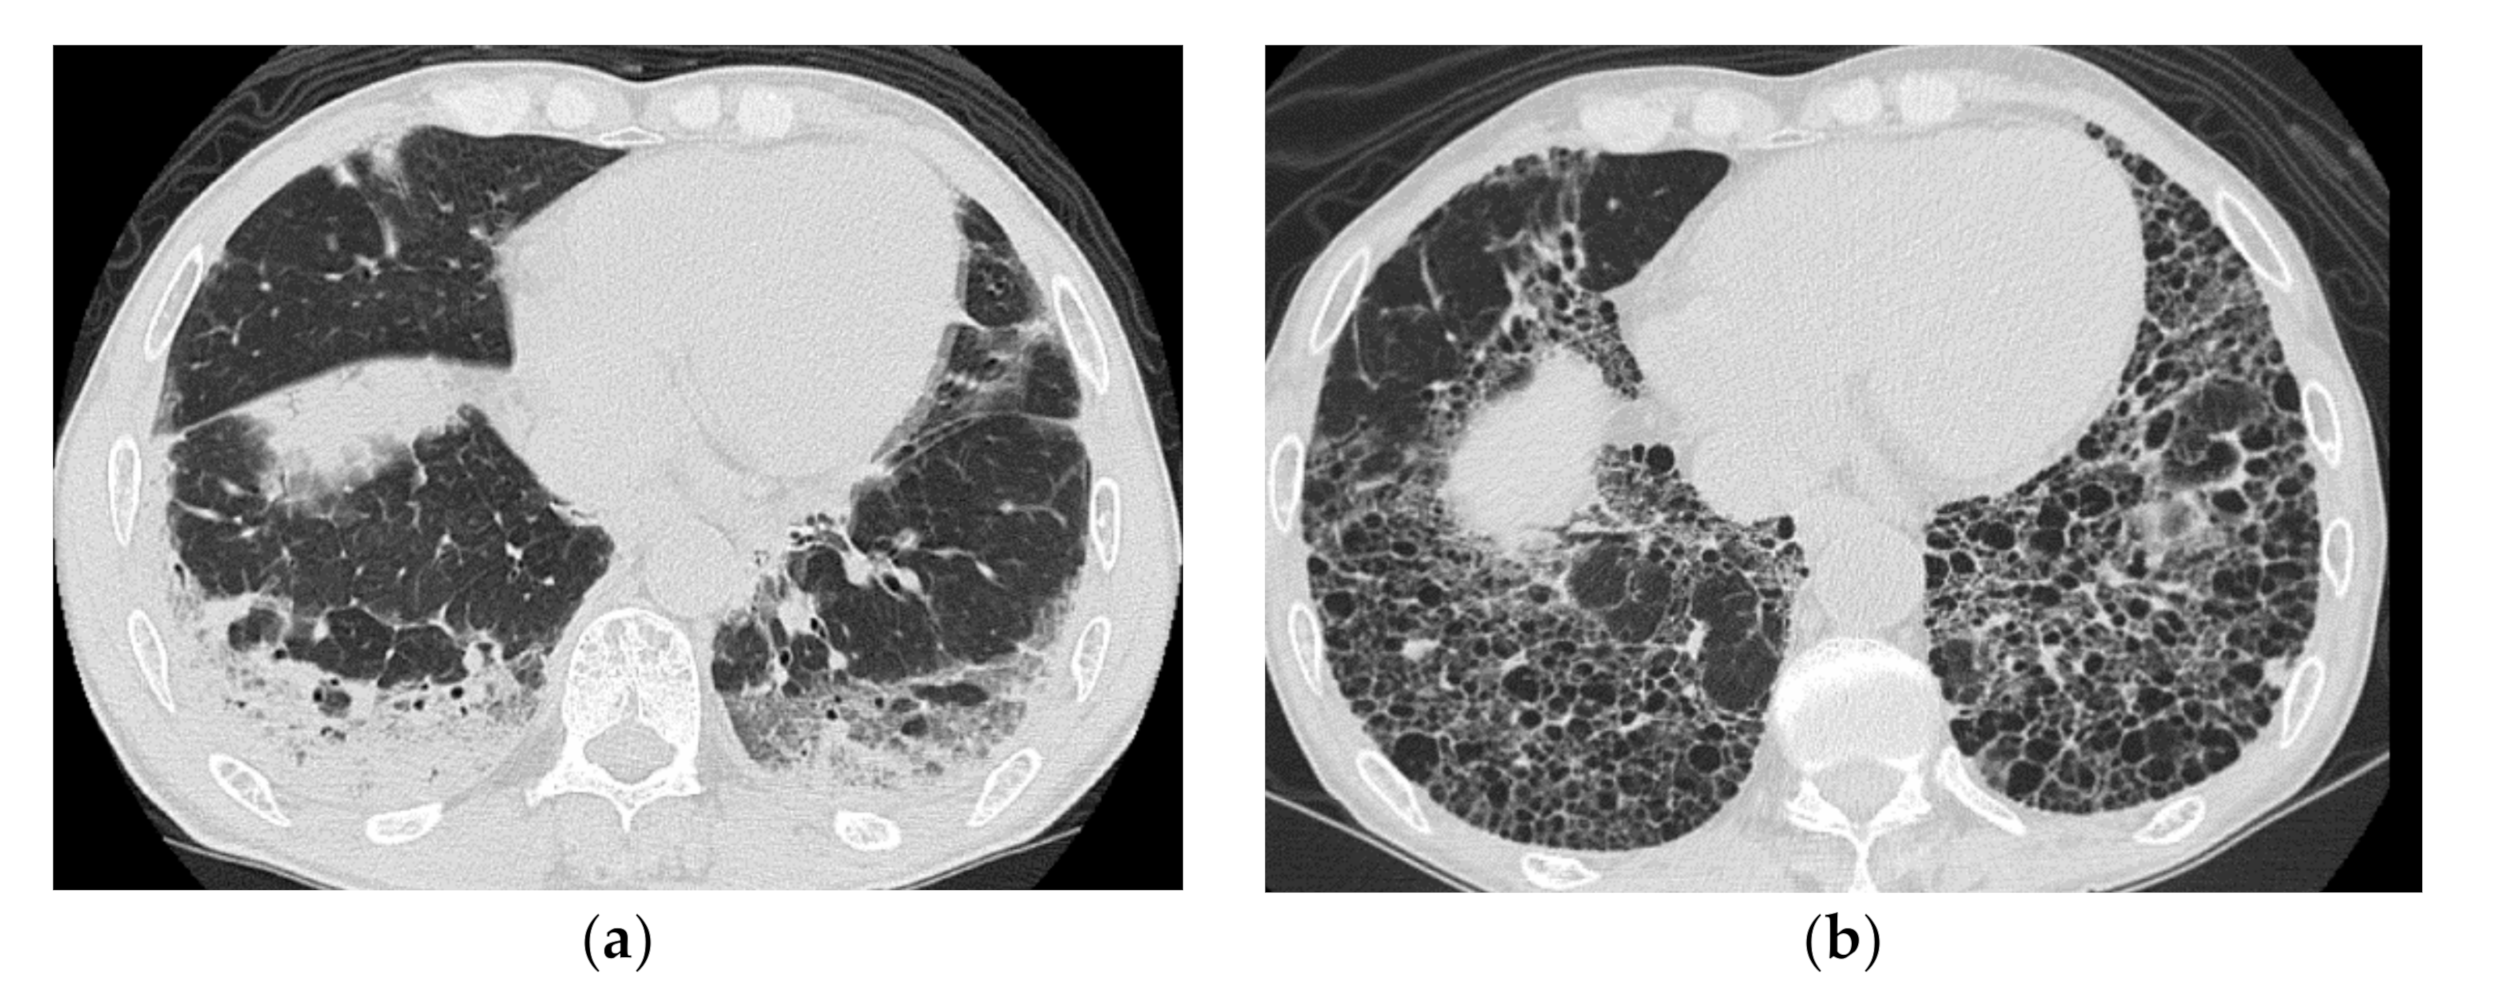

2.2. Acute Type

| Chronic to Subacute | Acute |

|---|---|

| Subacute course of disease > chronic | Acute or subacute onset, often with a rapid progressive course |

| Predominantly in the lower lobes of both lungs | Diffuse, or diffuse with a predominance of the lower lung zone |

| Peribronchovascular bundle distribution | Peribronchovascular distribution in the lower lobes, with parallel extension to the pleura |

| Reticular shadows and consolidation are common | GGO and consolidation |

| Reduced volume of the lower lobes | Basal volume loss |